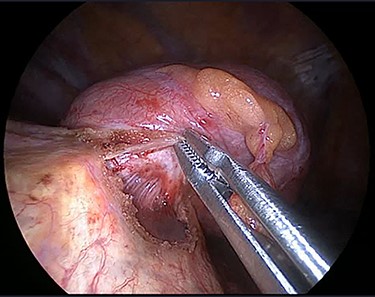

The operation was performed under general anaesthesia with the patient intubated using a double-lumen endotracheal tube. A 4 cm incision was made in the right sixth intercostal space in order to locate the mass. After the insertion of a 10 mm 30-degree thoracoscope, a rounded smooth-surfaced, broad necked mass attached to the right hemidiaphragm was visualized (Fig. 3). The decision to open the diaphragm was made. Further dissection and exploration with an energy device revealed that the mass which was bounded superiorly in the form of a pouch by the diaphragm and had arisen from the liver (Fig. 4). The mass was completely resected with HARMONIC ACE® +7 (Ethicon) after consulting with the hepatobiliary surgeon who felt there was a clear cleavage plane between the mass and liver. The exposed area of liver was covered with Floseal®(Baxter) and TachoSil®(Takeda). The diaphragmatic defect (Fig. 5) was closed in a single layer with 10 simple interrupted silk sutures (Fig. 6). The remainder of the surgery was uncomplicated, and the patient was discharged home on the second postoperative day. Subsequent histology findings reported the mass as benign (accessory) hepatic tissue (Fig. 7).